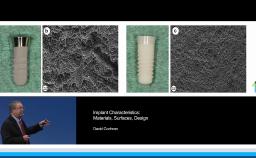

This lecture discusses the possibilities of hydrophilic SLActive implants. It describes the development of this technology in detail and also presents the existing evidence for the SLActive surface from both in vivo and clinical studies. The results of multiple animal studies are presented to demonstrate the significantly enhanced osseointegration compared to non-hydrophilic surfaces. Also presented are the results of a randomized controlled prospective human clinical trial comparing outcomes for SLA and SLActive surfaces. Finally, the lecture introduces the benefits of the titanium-zirconia (Ti-Zr) implant, which can expand the available treatment modalities in implant dentistry.

- describe the surface characteristics of titanium-zirconia (Ti-Zr) implants